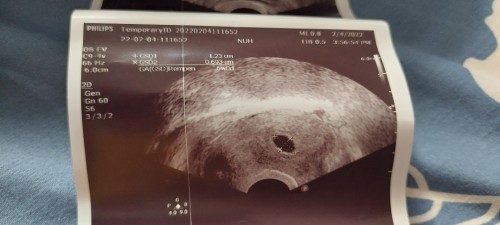

I am 7th wk of pregnancy but doctor said in the scanning only yolk sac is growing inside no baby seen no fetal pole in the 5th wk scan they told same no detail pole only yolk sac is growing now 7th wk scan the same yolk sac is growing only but fetal pole I don't know what to do for that .. what to do next #pleasehelp #firstbaby #1stimemom #advicepls #pregnancy #bantusharing